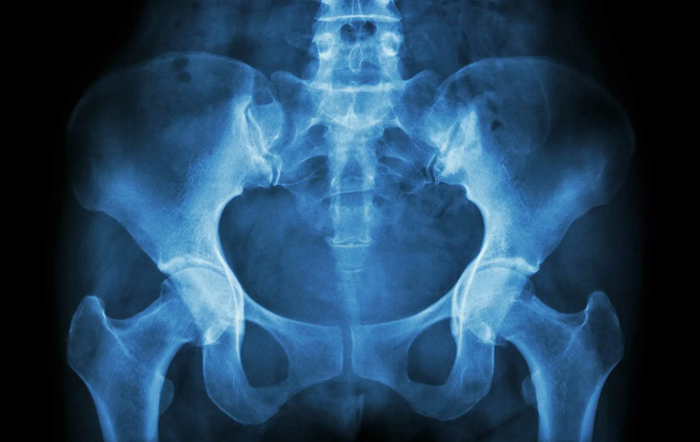

Расшифровка результатов рентгена таза показывает:

- состояние тазобедренных костей – наличие переломов, трещин, также шейки бедра;

- подвывихи и вывихи;

- дегенеративные процессы - например, коксартроз;

- воспалительные процессы - артрит и остеомиелит;

- отклонения от нормы плотности костной ткани - например, остеопороз;

- новообразования с повышенной плотностью тканей;

- дегенеративные процессы хряща.

Расшифровка результата занимает около часа. В заключении указываются отклонения от нормы.